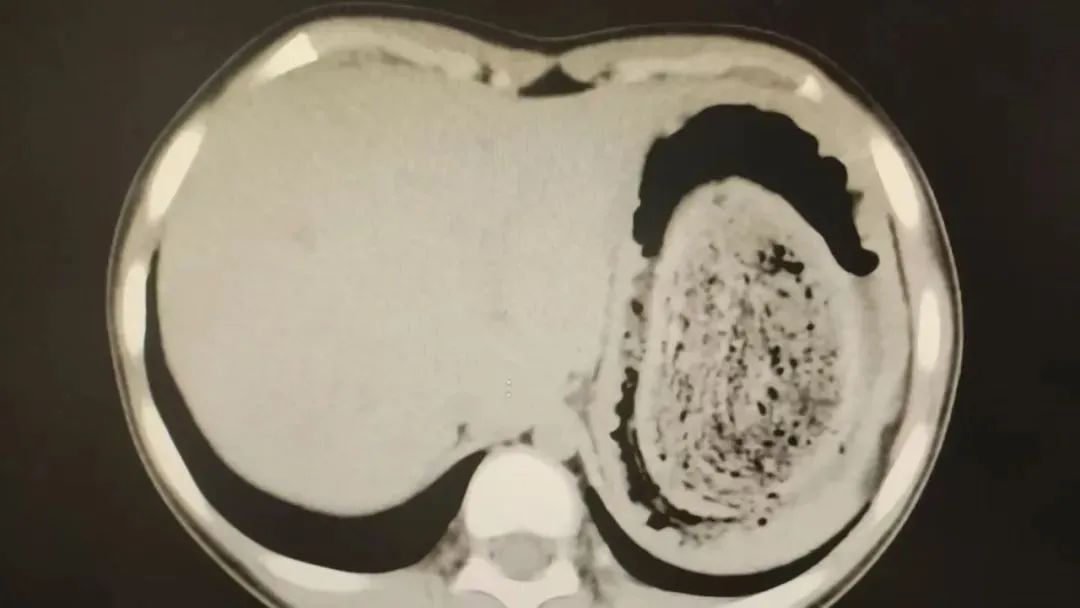

前不久,今年10岁的园园(化名)因持续3天的上腹痛伴呕吐被紧急送医。影像学检查结果显示,她的胃部存在一个巨大的团块状阴影,初步怀疑为异物堵塞。

据主刀医生陈杰介绍,园园的情况较为复杂,胃内的头发团块体积庞大,占据大部分胃腔,严重影响了食物摄入。更棘手的是,部分毛发已进入小肠,引发消化道梗阻。单纯通过胃镜或传统的开放手术难以同时解决两个部位的异物问题,因此选择腹腔镜微创手术,力求在最小创伤下彻底清除异物。

经检查,医生发现她胃腔和肠管里有大块的毛絮状结石。几乎占据整个胃部,不及时解决或将引发严重并发症。专家会商并为欢欢制定腹腔镜手术,最终,一块长38厘米、宽15厘米、厚10厘米的毛发结石被取出。